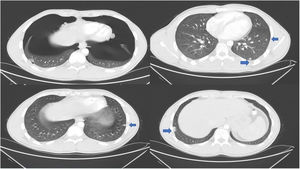

An 18-year-old male patient was admitted to the hospital with a palpable approximately 10cm mass lesion on the lateral side of the gastrocnemius muscle of the left lower extremity. The mass of the patient who did not detect distant metastases as a result of positron emission tomography (PET/CT) was surgically excised. As a result of the pathological evaluation of the material removed after the operation, it was reported that the mass was synovial sarcoma. Six courses of IMA (ifosfamide, mesna, adriamycin) treatment was planned. Six months after the completion of adjuvant therapy, multiple lung nodules were detected on thoracic computed tomography (CT). New systemic treatment was planned for the patient for recurrent synovial sarcoma. Primary granulocyte colony-stimulating factor (G-CSF) prophylaxis with gemcitabine and docetaxel treatment was planned as second-line chemotherapy. Despite the primary prophylaxis, the patient could not tolerate chemotherapy due to deepening bi-cytopenia, and the patient's systemic treatment was discontinued due to toxicity. Pazopanib was started as a third-line treatment. The radiologic evaluation was performed after 3 months of treatment in the patient, who did not detect any toxicity with pazopanib treatment and did not have any complaints. Bilateral significant pneumothorax was detected in the CT performed to evaluate the response. Diffuse bilateral pneumothorax is shown in Fig. 1. Despite bilateral significant pneumothorax, the patient did not have any clinical deterioration. The patient was treated with tube thoracostomy and he was discharged after five days of hospitalization. Pazopanib was restarted at 400mg/day for two weeks after discharge. Systemic treatment of the patient who developed pneumothorax again after one week of pazopanib use was completely discontinued.

Soft tissue sarcomas metastasize quite frequently. The lung is an important site of metastasis. Unfortunately, treatment options are limited in metastatic soft tissue sarcomas. Pazopanib is an effective treatment option for these patients. In a pre-approved clinical study of pazopanib for metastatic soft tissue sarcoma, the incidence of pneumothorax during pazopanib treatment was reported to be approximately 2%.3 However, higher pneumothorax rates (∼10%) have also been reported in more recent studies.4 The mechanism of secondary pneumothorax arising from lung metastases is not clear. However, various theories such as tumor necrosis, check valve and tumor embolism have been reported.4 In addition, it is well known that angiogenesis inhibitors cause tumor necrosis and cavitation in lung lesions.5 Pazopanib can also cause pneumothorax by using this mechanism of action. Especially in sarcoma patients with diffuse lung metastases, routine lung examination and chest X-ray should be planned even if there are no symptoms while using pazopanib treatment.